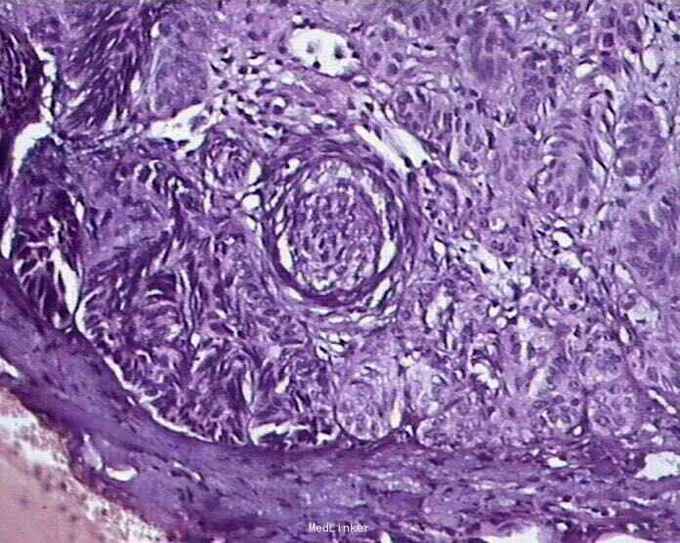

基底细胞癌

男性,62岁,鼻尖溃疡6个月。 6个月前鼻尖起一小丘疹,不痛不痒,随后中央溃破形成溃疡,外用抗生素软膏等无效。溃疡逐渐扩大,间有出血。

鼻尖1.2cm×1.0cm溃疡面,质中,边界不规则,基底不平,触之易出血。

手术切除加病理活检:皮肤基底细胞癌。

基底细胞癌常见于中老年人,发病与紫外线关系明确,当暴露部位出现慢性溃疡,常规处理不能使之愈合时应警惕本病。